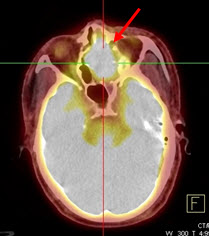

Hình 2. Bệnh nhân Trần V. V., nam, 57 tuổi. Chẩn đoán: u lympho hốc mũi; Giải phẫu bệnh: WF5. Hình CT, PET và PET/CT cho thấy tổn thương u ở vùng hốc mũi trái (mũi tên) tăng hấp thu FDG.